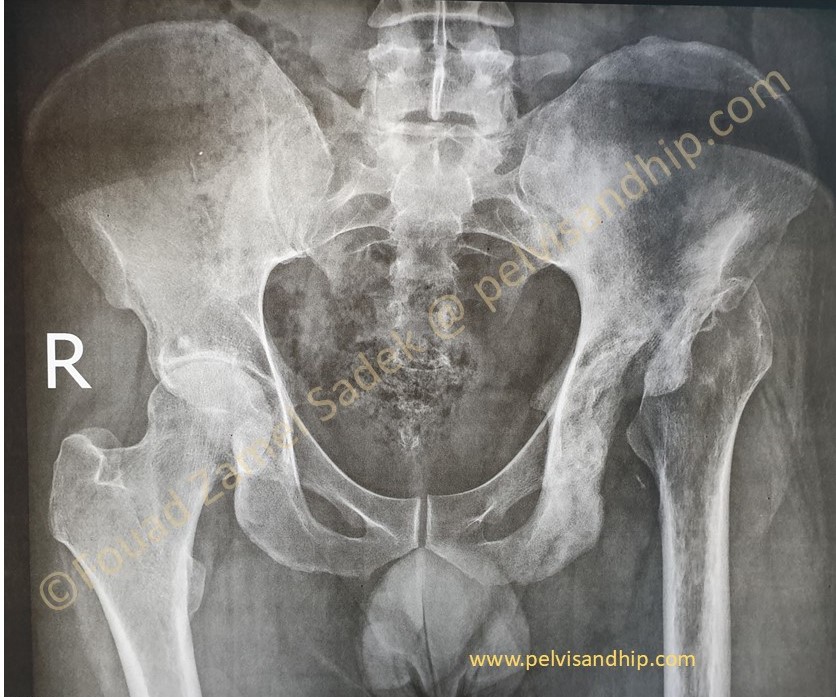

Case 10: A 34 years old female with chondrosarcoma of the right acetabulum, done in conjunction with our musculoskeletal oncology experts. Lady presented with pain in the right hip area. (Please click on the picture for further study of this case.)